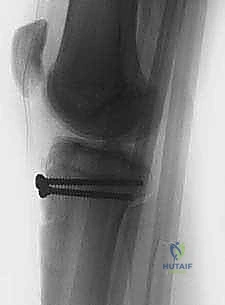

5. التثبيت الداخلي (Internal Fixation)

هنا تبرز مهارة الجراح في اختيار طريقة التثبيت التي لا تضر بصفيحة النمو (إذا كانت لا تزال مفتوحة).

* استخدام البراغي المجوفة (Cannulated Screws): يتم إدخال سلك توجيهي رفيع أولاً، وبعد التأكد من موقعه بالأشعة السينية داخل غرفة العمليات، يتم إدخال برغي أو برغيين من التيتانيوم القوي فوق السلك لتثبيت العظم. يحرص الدكتور هطيف على توجيه البراغي من الأمام إلى الخلف، وفي بعض الأحيان بزاوية مائلة لتجنب اختراق صفيحة النمو قدر الإمكان.